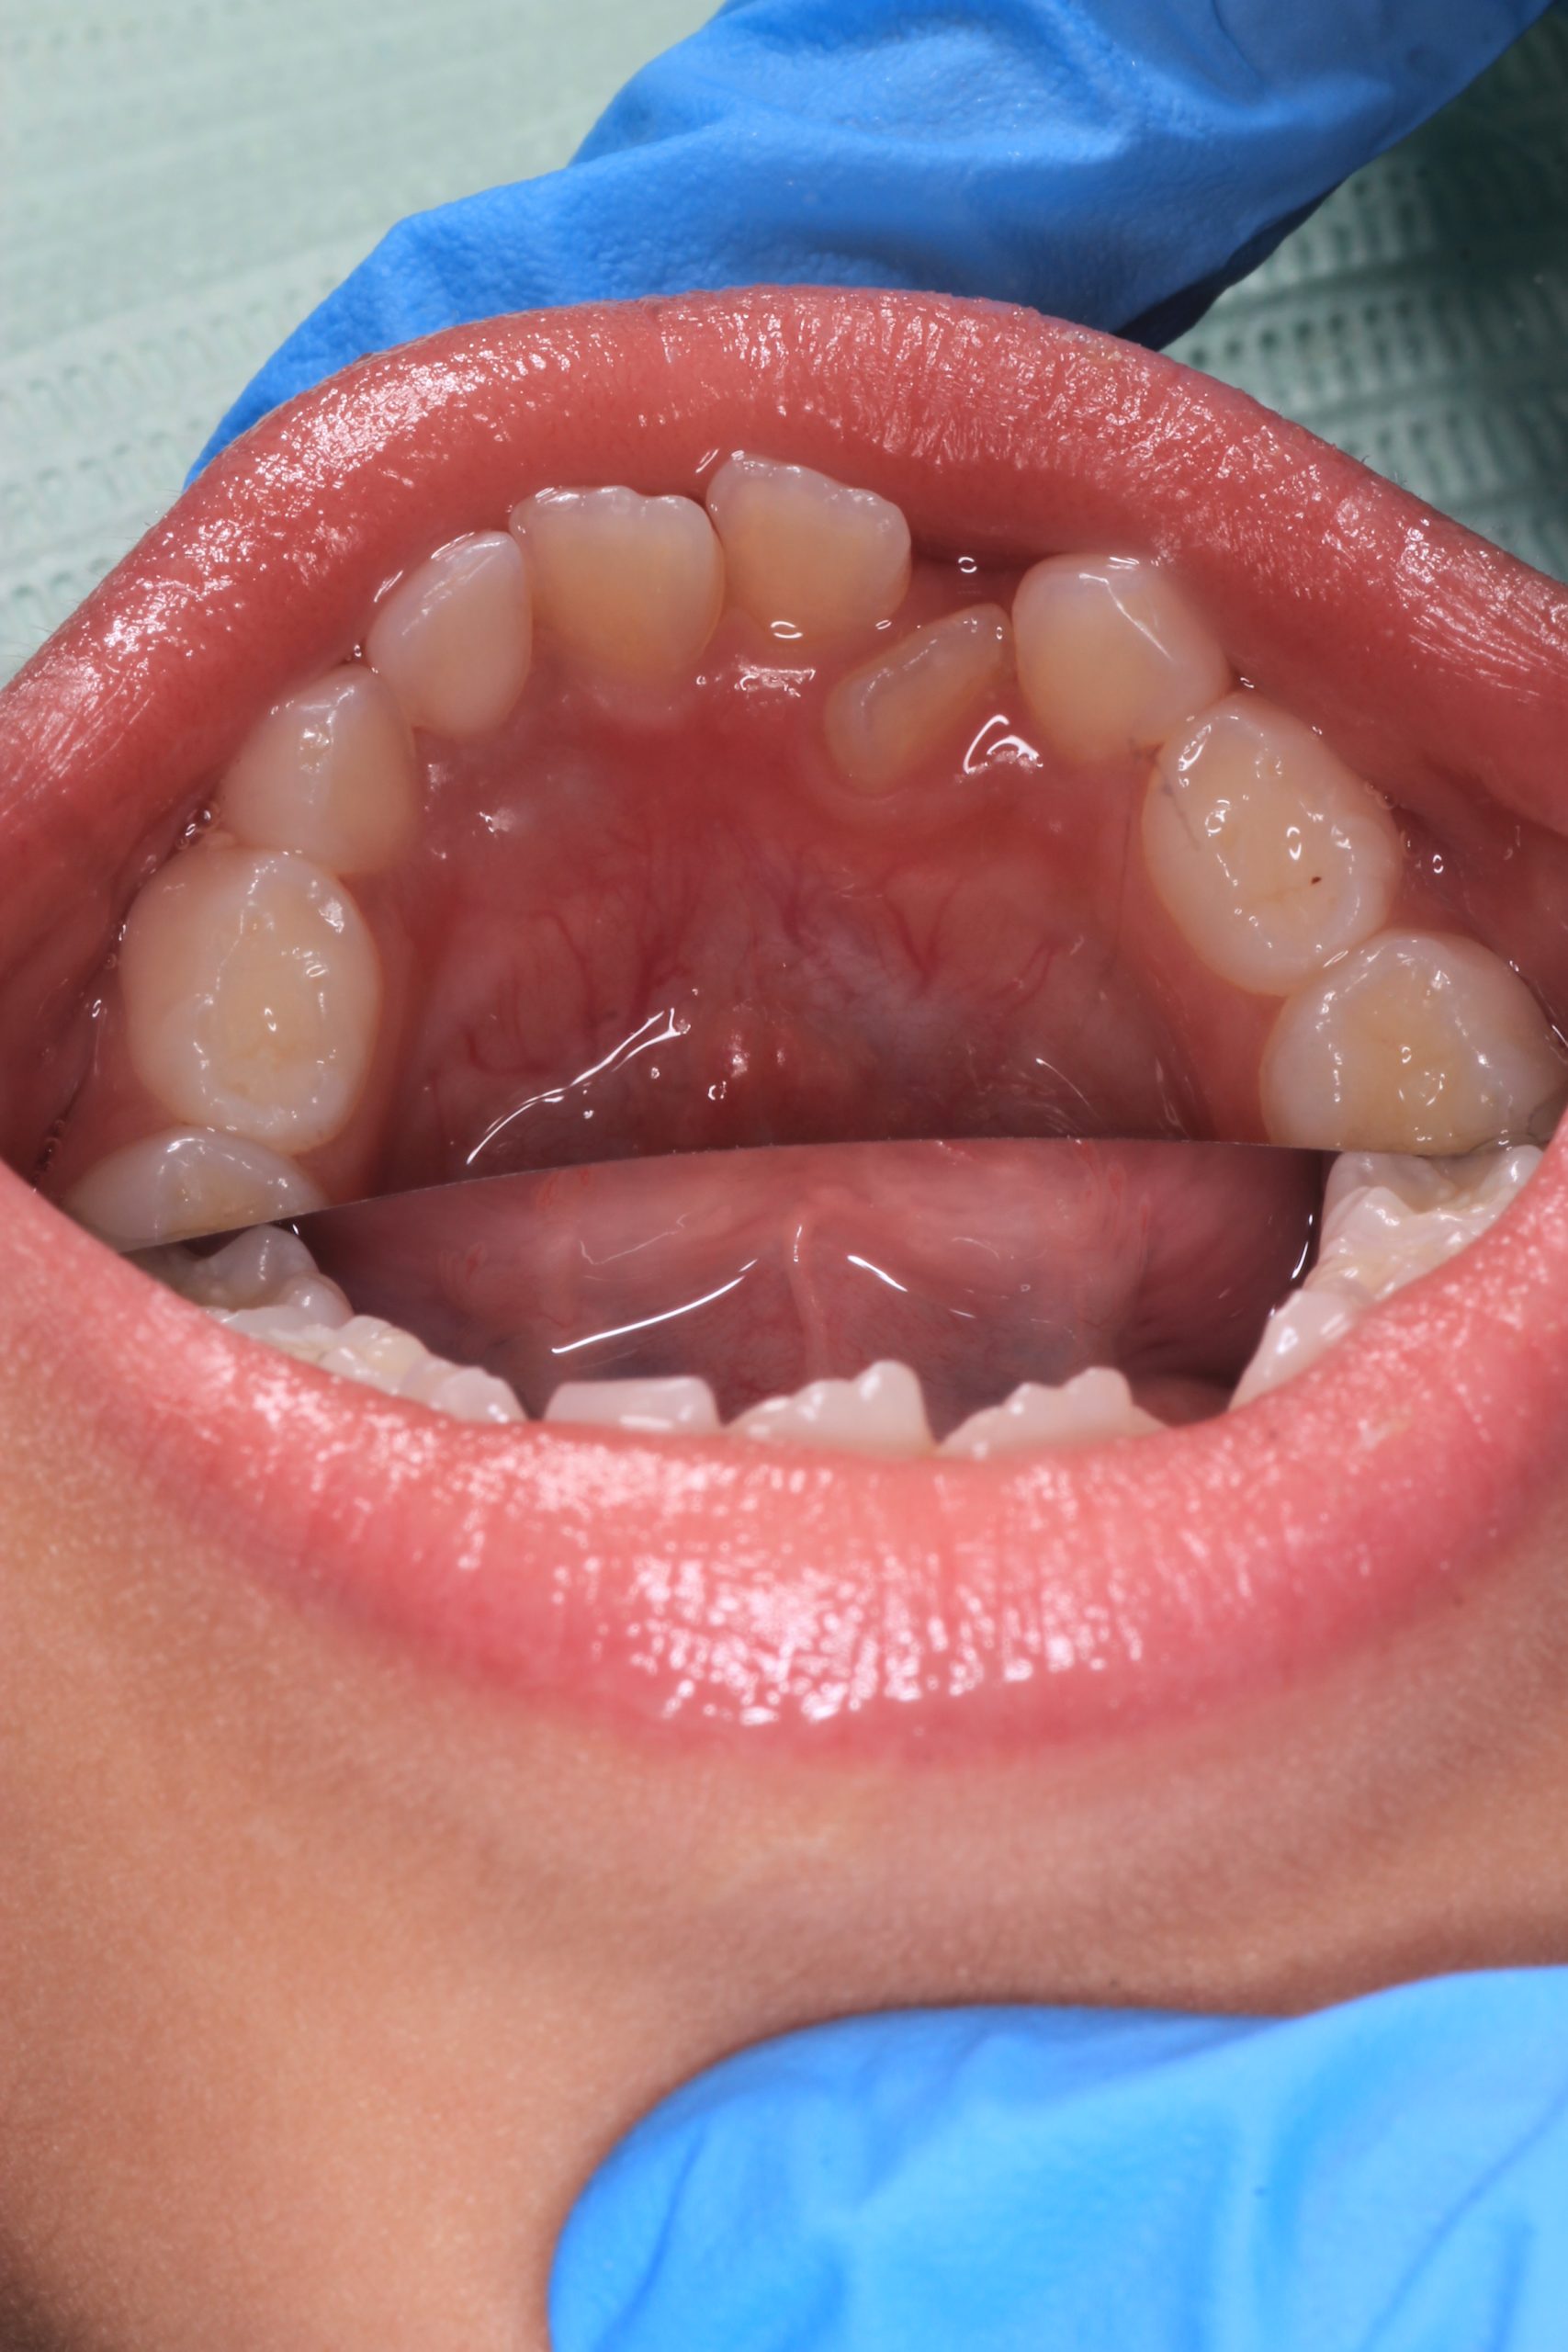

We examine the condition of teeth, gums, and bite. - Plaque Disclosure with Special Indicators

Areas that weren’t cleaned well appear purple. The darker the shade, the older the plaque. This helps both kids and parents understand where brushing needs to improve. - Brushing Training & Home Care Tools Selection